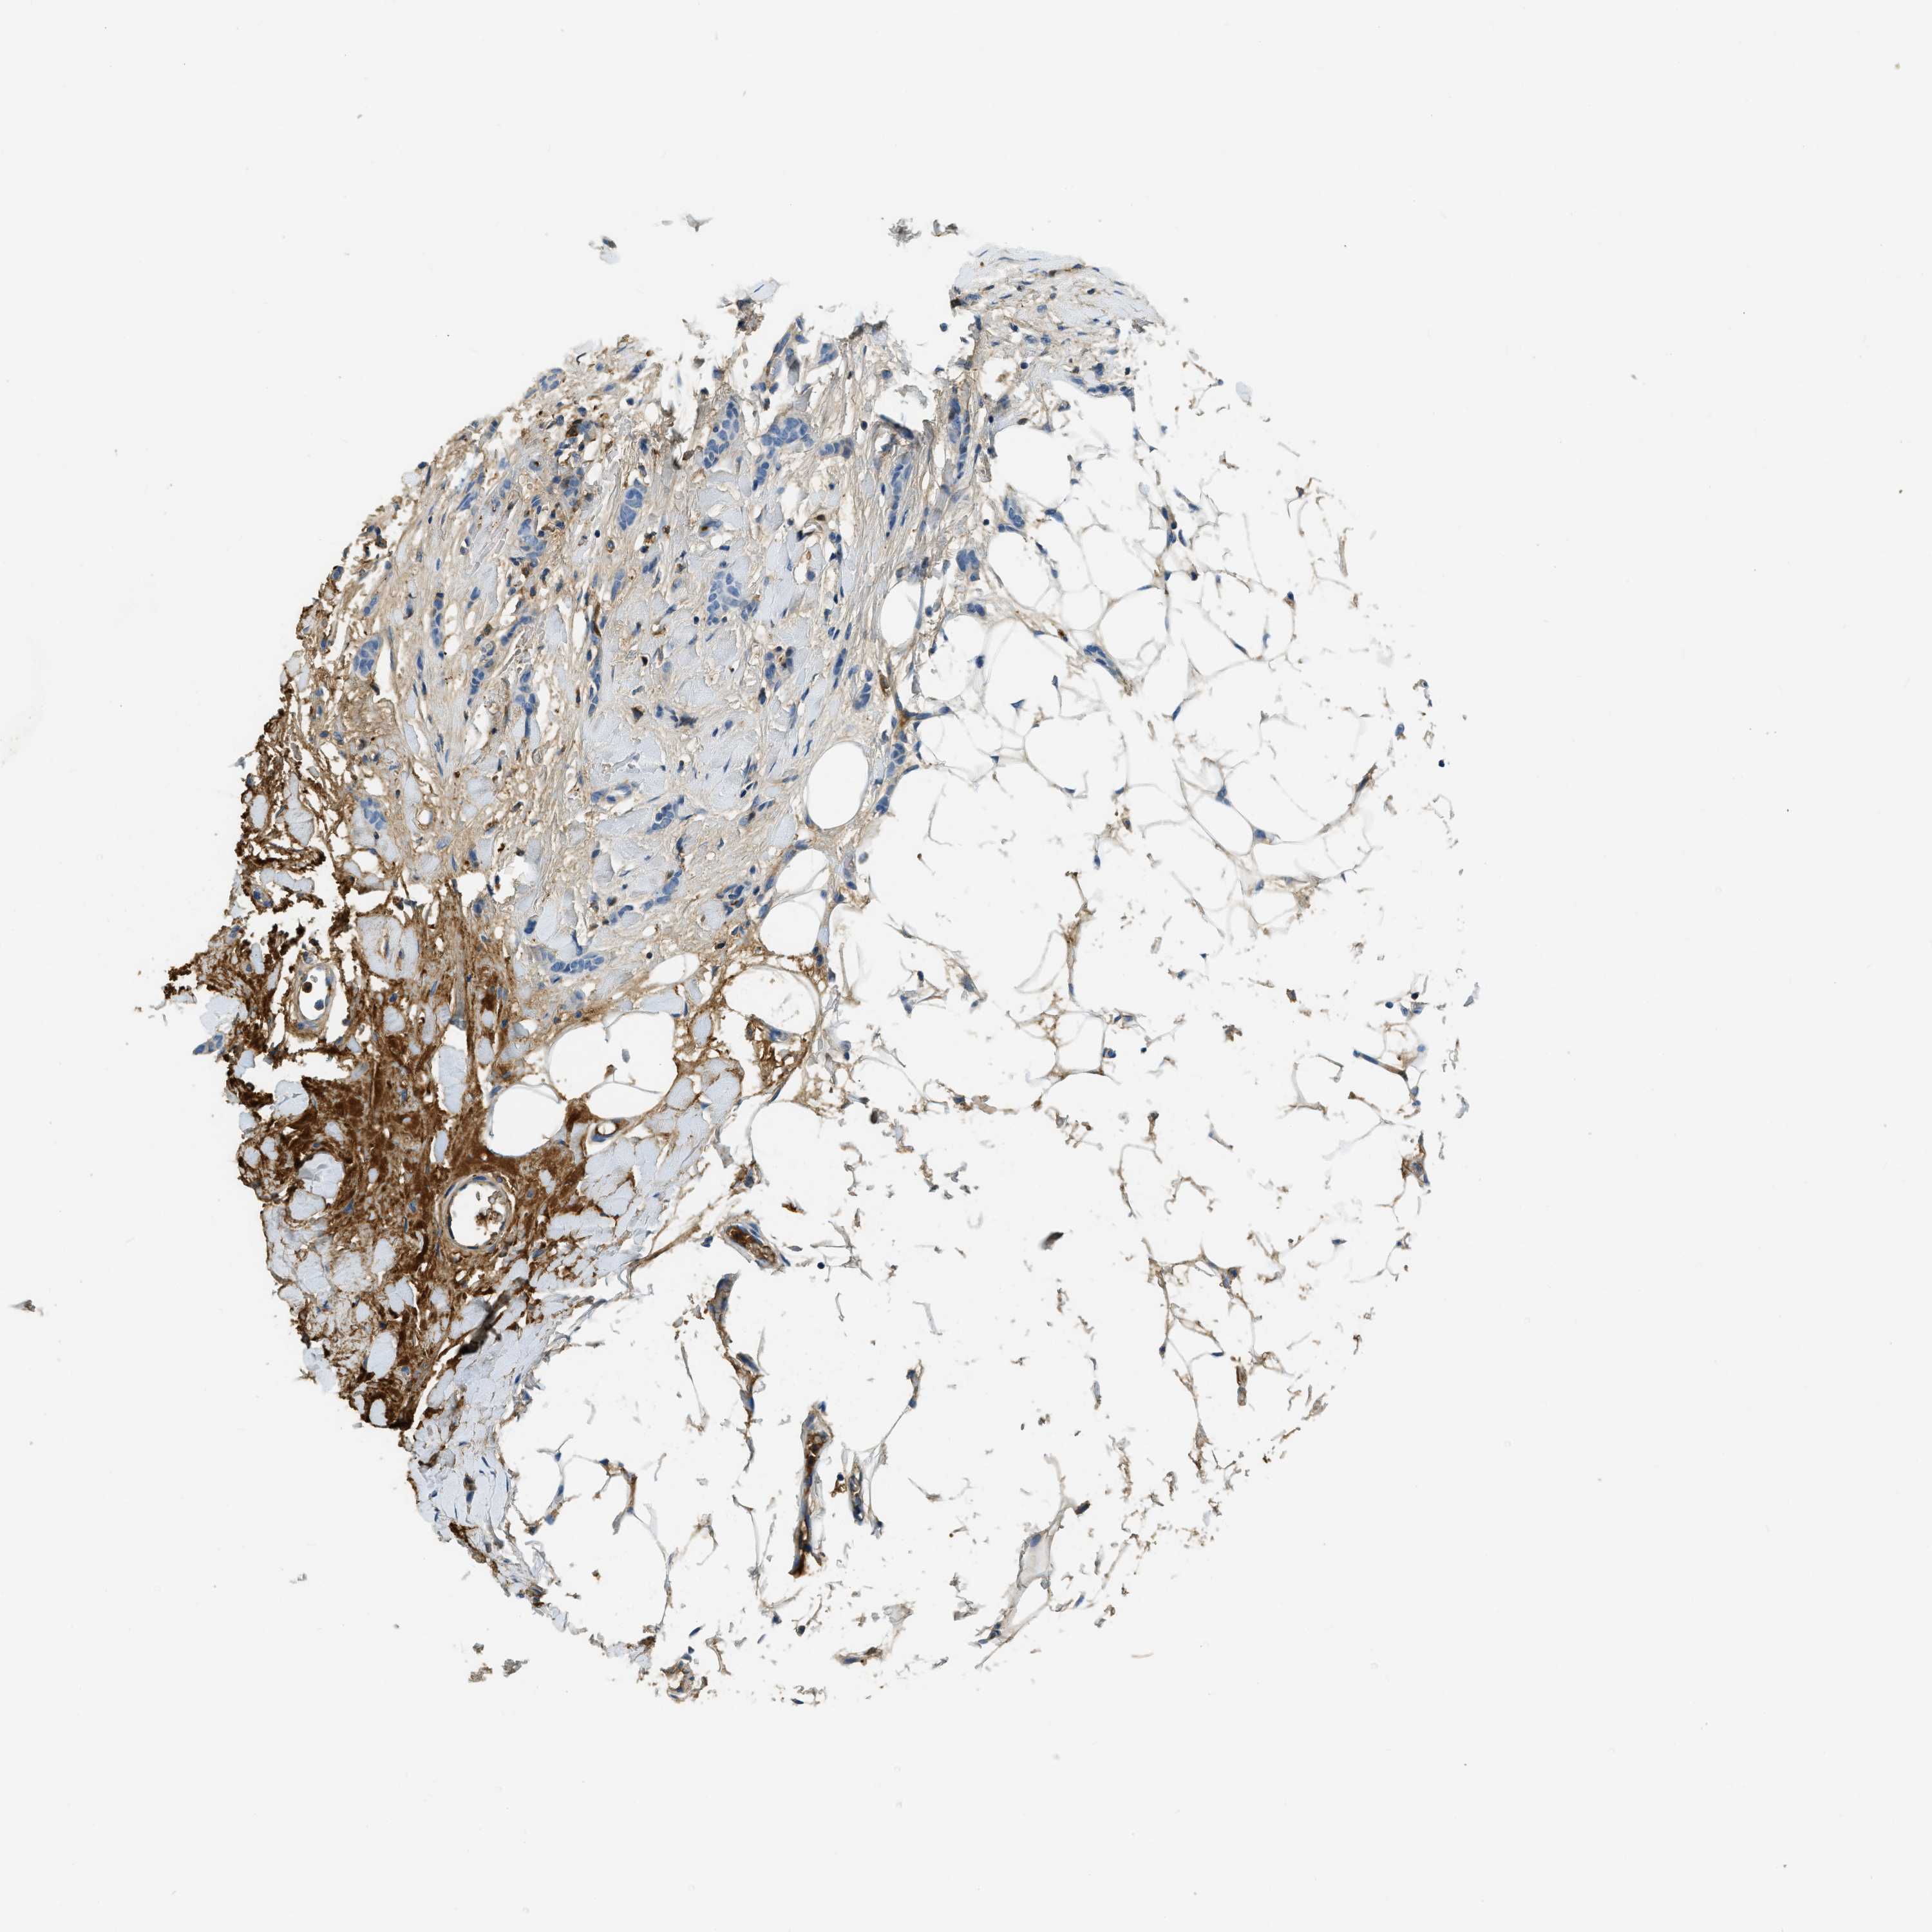

BRCA TCGA BRCA VALIDATION PROTEIN EXPRESSION

ANTIBODIES

AND

VALIDATION